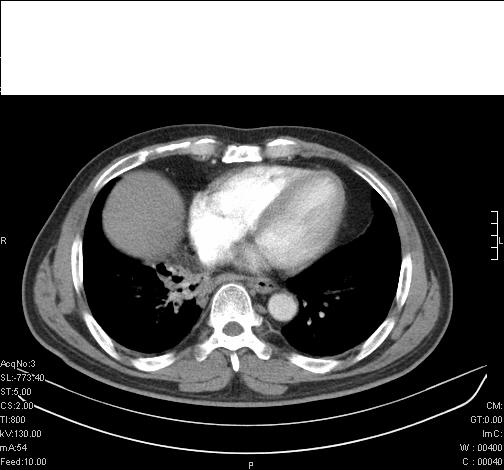

标题: CT6685:右肺阻塞性炎症,增强CT。 [打印本页]

标题: CT6685:右肺阻塞性炎症,增强CT。

前几天,发了患者的平扫片,患者抗炎一周后增强扫描。右中叶病灶吸收明显,但下叶病灶未见明显吸收。右肺门可见结节影,看来凶多吉少

右肺下叶支气管管腔狭窄,管壁增厚,右下肺见斑片状高密度影,考虑右侧肺门中心肺癌伴阻塞性肺炎

右肺下叶支气管壁明显增厚,考虑癌症并阻塞性炎症、肺门淋巴结肿大

考虑右肺癌并阻塞性炎症、肺门淋巴结肿大

右主支气管狭窄,管壁增厚。考虑右中心性肺ca伴阻塞性肺炎。

既然抗炎治疗有效,可继续治疗;右肺下叶支气管管腔狭窄,管壁增厚,右下肺见斑片状高密度影,右侧主支气管后见结节影(淋巴结?),肺癌不能排出。